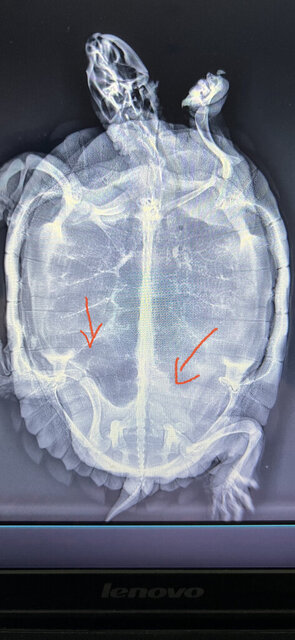

По рентгену напрягало 3 яйца параллельно, но сама она не хочет рожать, капароте перестала и греется ест и плавает, сделала в субботу укол, родила но 8 из 10, жду что ответит врач, что делать с оставшимися

В итоге ожидала 2 оставшихся а вышло 5,  через неделю начала активно ночью буянить и рыть днем и ночью мост, отвезла на рентген, новых яиц нет, хотя очертание слева ня мягкое ( может это уже только в моих глазах) после врача рыть и буянить перестала, кушает, плавает, греется но не какает, на рентгене ссужает справа в тазу светлое пятно, к врачу еще не обращалась, рентген делала оперативно в ближайшей ветеринарке где согласились. Если есть знающие как читать рентген хелп, в связи с праздниками к Марии Дмитриевне пока не могу записаться